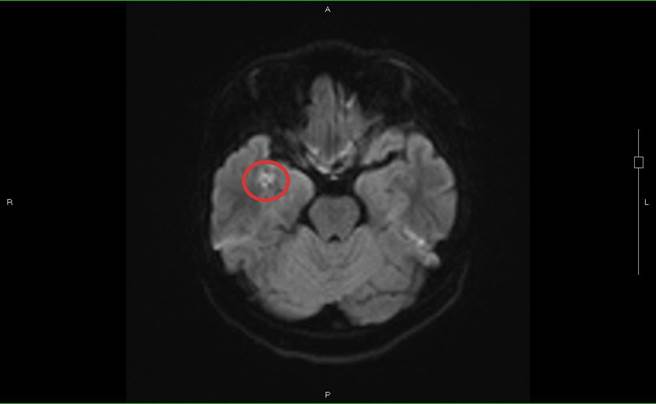

沈积在脑部右边颞叶脂肪粒(红圈处),导致少年出现情绪症状。(光田综合医院提供/陈淑娥台中传真)

严可伦解释,股骨(大腿骨)、胫骨(小腿骨)是人体的长形骨,骨头中央有着脂肪丰富的骨髓,当病患骨折时,这些脂肪粒从断骨处释放散出,随着血液回流后先经过肺臟,因此脂肪栓塞常常发生在肺部,病人会出现喘不过气、血氧降低等症状,但阿成完全没有肺部症状,脂肪意外卡在脑部。

黄炳钟说明推测病患可能年轻,骨髓中的脂肪粒微小,通过肺部后再随血液至脑部而沉积在左边额叶及右边颞叶,这两处都与情绪处理相关连,因而出现情绪症状。